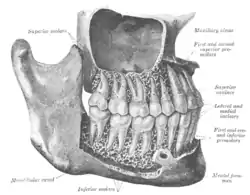

The permanent teeth, viewed from the right | |